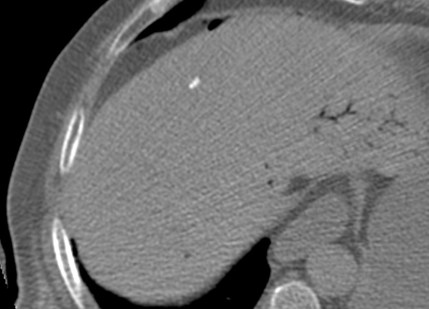

Se realiza TC de abdomen en vacío y con contraste en fase portal:

Estamos ante un cuadro de isquemia intestinal en un paciente con bajo gasto cardiaco con afectación principal de asas intestino delgado, territorio vacularizado por la arteria mesentérica superior.

5º) Neumatosis intestinal y portal. Aire extraluminal.

Son signos poco frecuentes pero muy específicos de isquemia intestinal, E cercana al 100%. Se obsevan mejor en el TC SIN contraste.

La neumatosis intestinal consiste en aire localizado en la pared del intestino. Se produce por discontinuidad de la pared con paso de aire hacia las capas más externas y a las venas intramurales.

La presencia de neumatosis portal y mesentérica consiste en pequeñas burbujas de gas dentro de los vasos mesentéricos o que también pueden extenderse hacia las ramas intrahepáticas de la vena porta, encontrándose típicamente en la periferia del hígado.